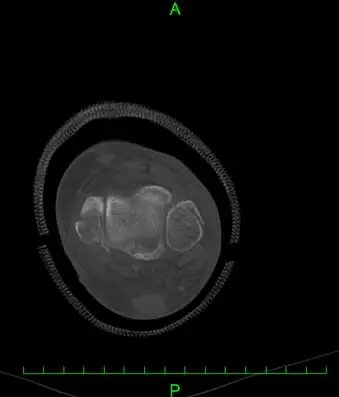

(図2)CT

足関節内外果骨折、脛骨天蓋部に5mmのstep offを伴う陥没骨折と踵骨アキレス腱付着部より1.5cm近位に骨片を認める。